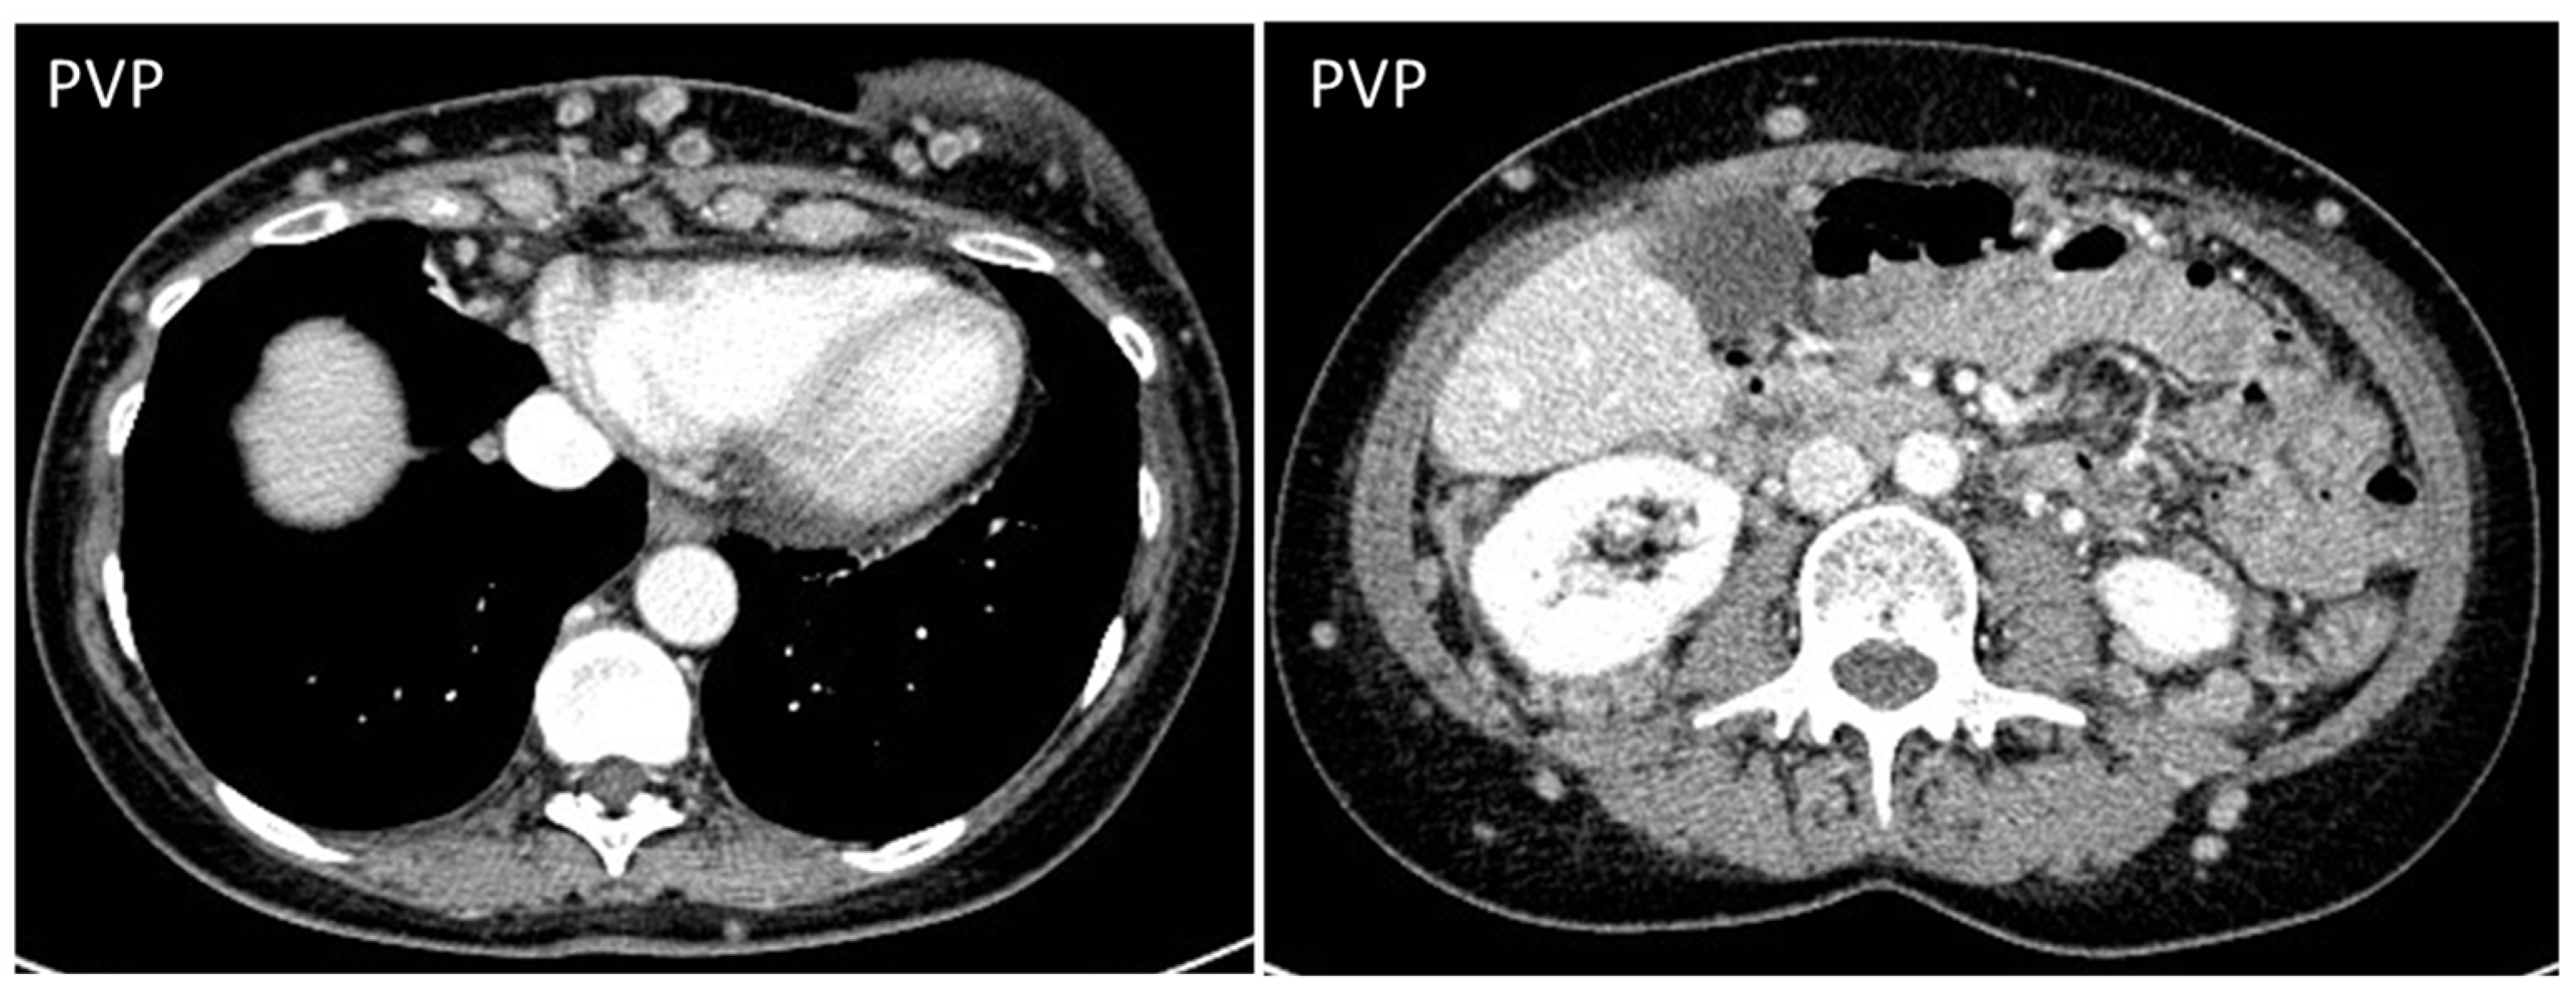

- Gastrointestinal Stromal Tumors (GIST): either primary (extraintestinal GIST, “EGIST”) [25,26] or secondary GIST of the abdominal wall are rare. When extended (>5 cm), GIST may have an aggressive behavior [25]. CT is the imaging modality of choice, showing heterogeneous vivid enhancement, and variable amount of necrosis. Peculiar findings include calcifications and cystic degeneration [27,28,29].